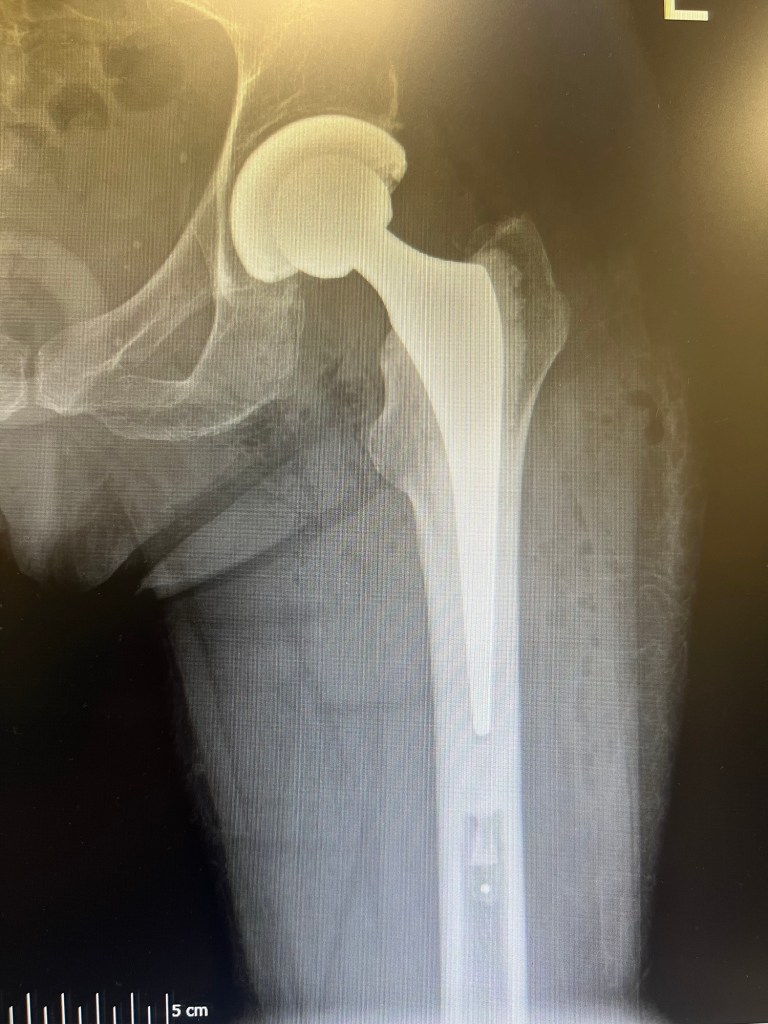

Mr Dehne Approach to fast recovery in joint replacement surgery

Following deep discussions, Mr Dehne developed, Based on development of ERAS principles, his principles of fast recovery in orthopaedic surgery. These principles are:

2. Minimal tissue disruptions during surgery

3. Process innovation in surgery, each surgical step is thoroughly improved to achieve efficient surgical process.

4. Carefully developed injections during joint replacement surgery, these are injected to achieve pain relief, reduce blood loss.